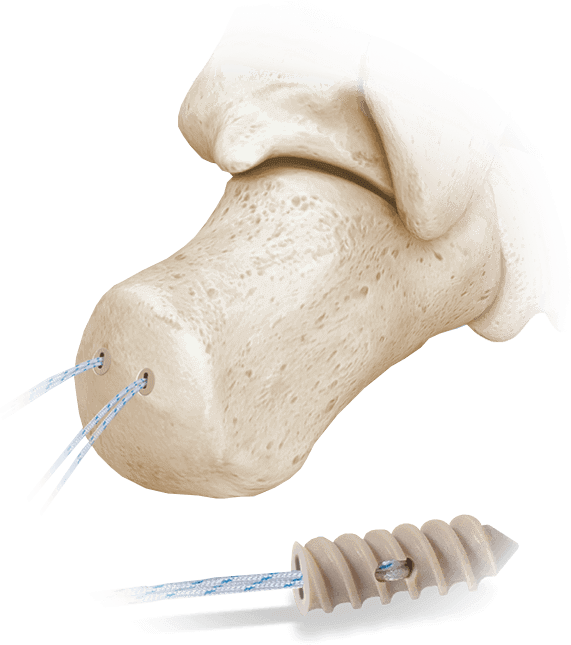

Hercules® Fully Threaded Suture Anchor System

PEEK anchor with Bightforce™ Suture for a range of soft tissue fixation applications.

Applications:

- Achilles tendon repair

- Midfoot and metatarsal ligament reconstruction

- Soft tissue reattachment in the hindfoot and forefoot

Key Advantages:

- Available in 2.0mm, 2.5mm, 3.5mm, 4.5mm, and 5.5mm sizes

- Radiolucent PEEK for imaging clarity

- Delivered sterile, preloaded with BightForce™ suture, and assembled to a driver

- Designed for excellent pullout strength and secure fixation